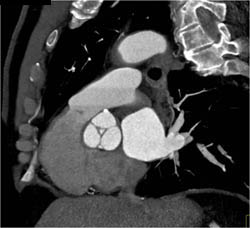

Dilated Ascending Aorta